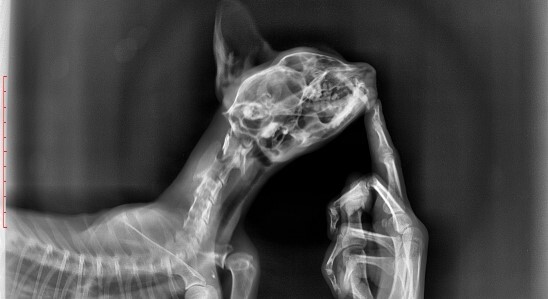

Большая часть зайчат умирает "внезапной смертью" вызванной отказом работы внутренних органов, сопровождаемым сильными болевыми ощущениями. Это происходит от обострения хронических проблем, которые копились из-за ошибок в выращивании (некрозы жкт, кровоизлияния в сердечно-сосудистой системе, переломы, защемления нервов, болезни ЦНС и другое). Дикие животные инстинктивно скрывают любое недомогание.